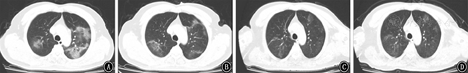

2020年1月27日双肺外带见片状磨玻璃影,符合典型的COVID-19演化特征[11];1月30日与1月27日对比:病灶呈游走性改变,总体较前增多;2月5日与1月30日对比:双肺病变吸收好转;2月8日与2月5日对比:双肺病变略显好转,胸膜轻微肥厚粘连。具体情况见图2。